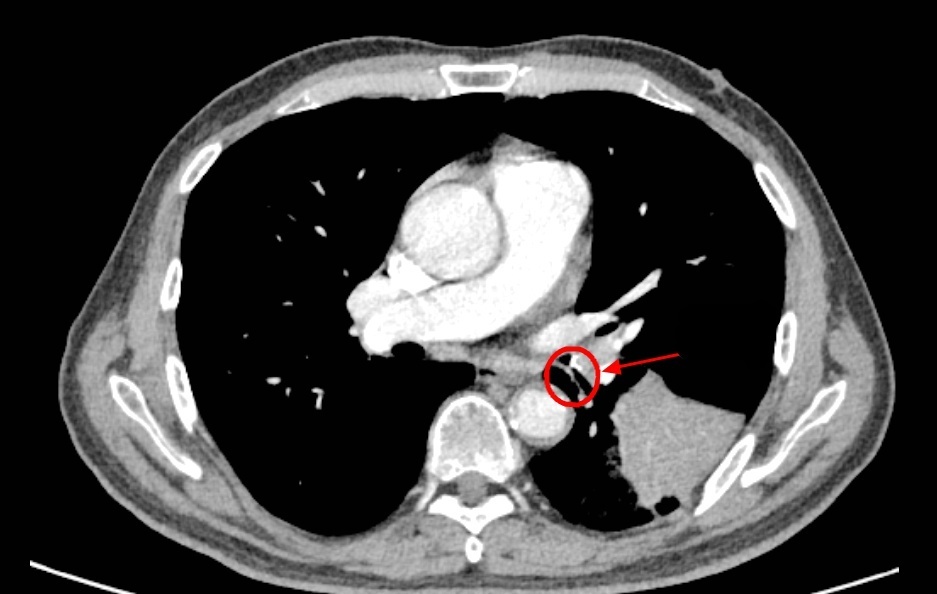

然而,从那天起,李老伯的咳嗽次数明显增多,而且还伴有浓痰,家人便带着李老伯到南京市第一医院河西院区呼吸与危重症医学科门诊就诊。胸部CT结果显示李老伯左肺下叶出现了一片“占位性病变”!

入院后,医生敏锐捕捉到一个关键细节:李老伯既往有明确的饮食后呛咳史,且此次发病前有吃鱼后呛咳的经历。因此判断,这应该不是肺部感染肿瘤,高度怀疑是气道异物,要对李老伯进行支气管镜检查!

竟意外发现在一片因炎症而充血水肿的支气管黏膜中,一个细长、坚硬的异物正死死地卡在管腔内,周围包裹着大量的脓性分泌物。

图片

原来竟然是一块长约1.6厘米的鱼骨!至此,真相大白。所谓的“肺部占位”,正是因为这块鱼骨堵塞气道,引发了堵塞性肺炎肺不张,导致李老伯长达半个月的咳嗽和咳痰。